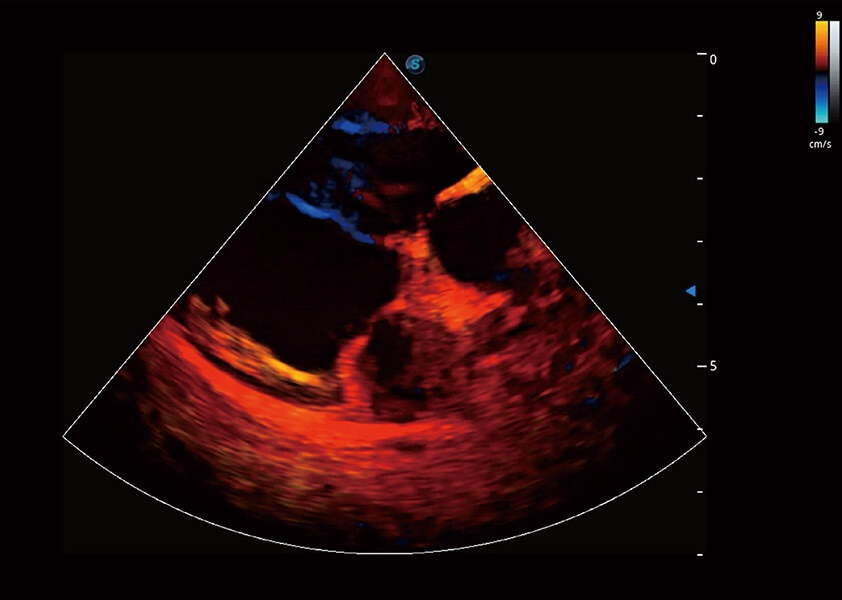

ProPet 60 作為一款高端臺(tái)式動(dòng)物超聲設(shè)備,為動(dòng)物醫(yī)生的日常診斷提供了一系列貼合動(dòng)物臨床需求、解決臨床實(shí)際問(wèn)題的高級(jí)成像功能。憑借全系列高清探頭,滿足醫(yī)生對(duì)腹部、心臟、生殖、淺表、肌骨等成像的所有需求,切實(shí)幫助您提升檢查效率,提高診斷信心。